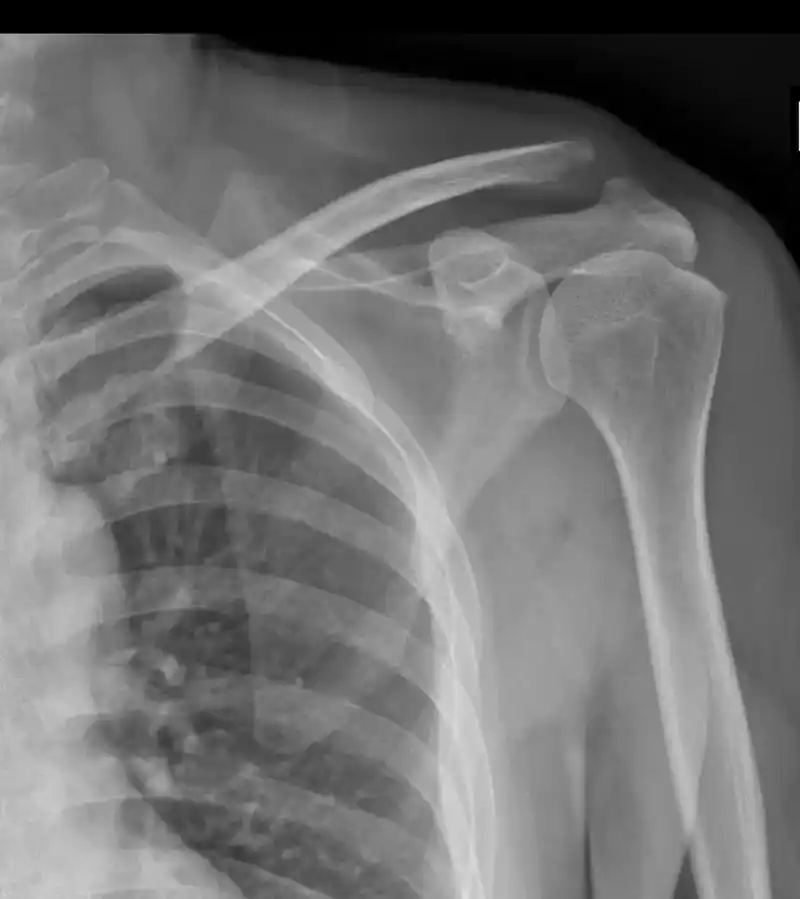

女子3年内肩关节脱位20多次医生取自体髂骨为其根治

视频教学:简单实用"外展外旋法"复位肩关节前脱位